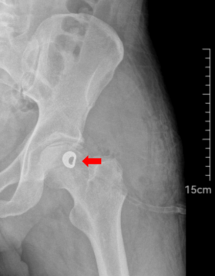

最近一段时间,冯先生左侧髋关节的疼痛感逐渐加重,前往哈尔滨市第五医院骨坏死门诊寻求治疗。哈市五院手外科一病区副主任聂广辰结合影像检查结果及ARCO分期(股骨头坏死分期)评估,诊断冯先生为左侧股骨头缺血性坏死(ARCO Ⅱ期)。影像学显示其股骨头内已出现局限性坏死病灶,囊性变,骨小梁结构受损,但股骨头轮廓尚完整。考虑到冯先生正值中年,对髋关节功能需求较高,决定为其实施显微外科保髋手术。

术后影像检查显示,钽伞与骨瓣位置精准,镁螺钉固定牢固,股骨头轮廓完整,坏死区域修复效果理想。目前冯先生恢复状况良好,髋关节疼痛症状已明显减轻,在医护人员指导下开始进行早期功能康复训练。